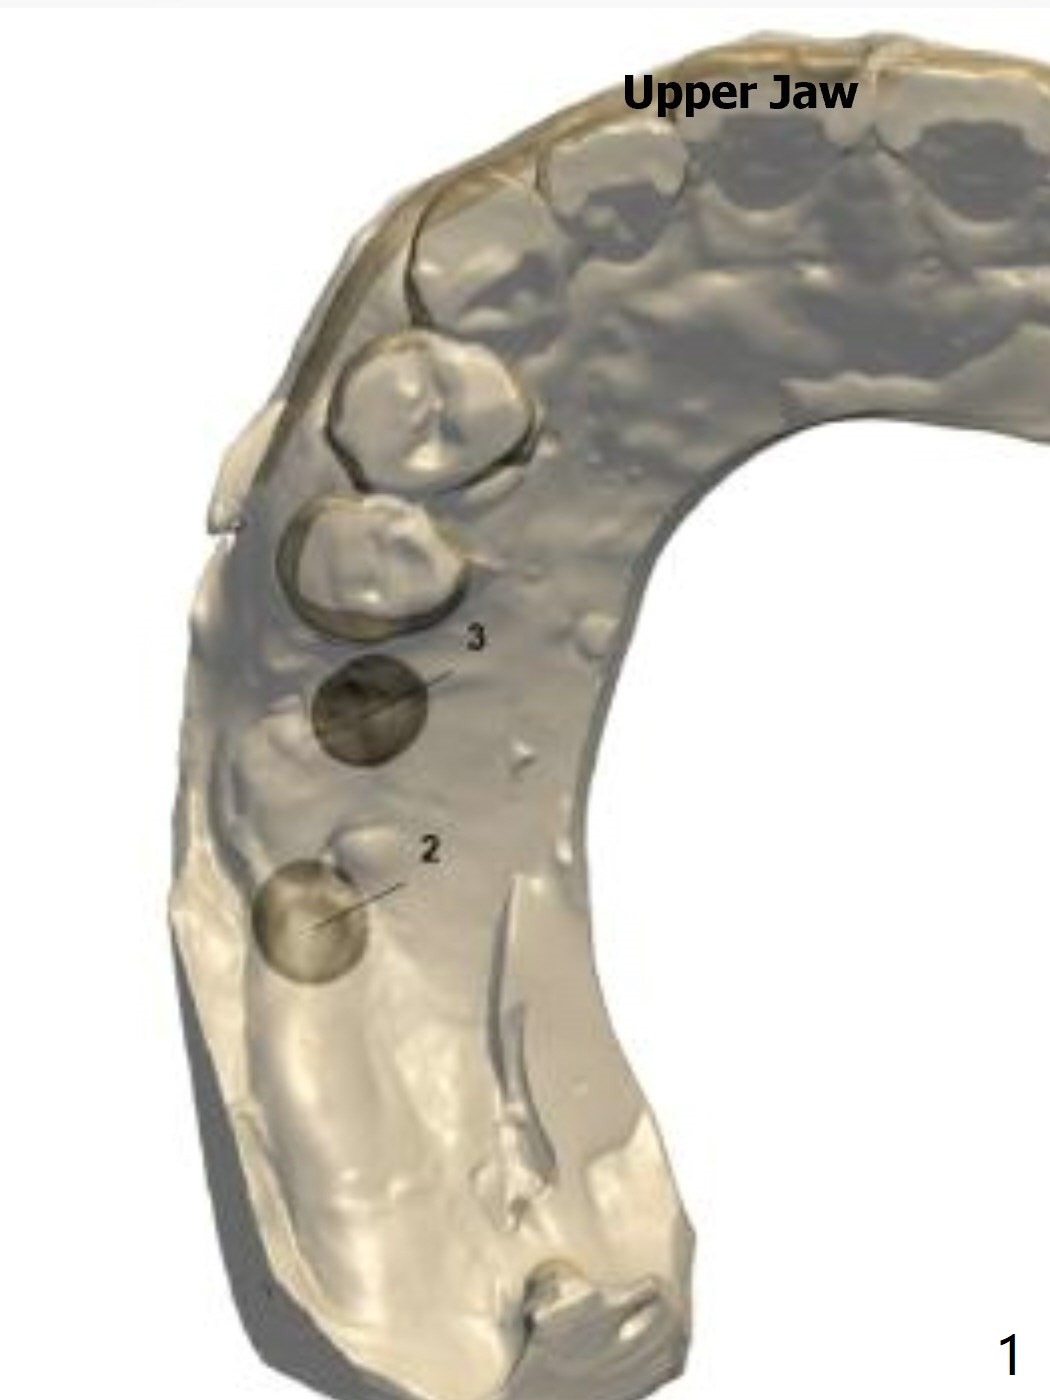

Return to Upper Molar Immediate Implant, Trajectory